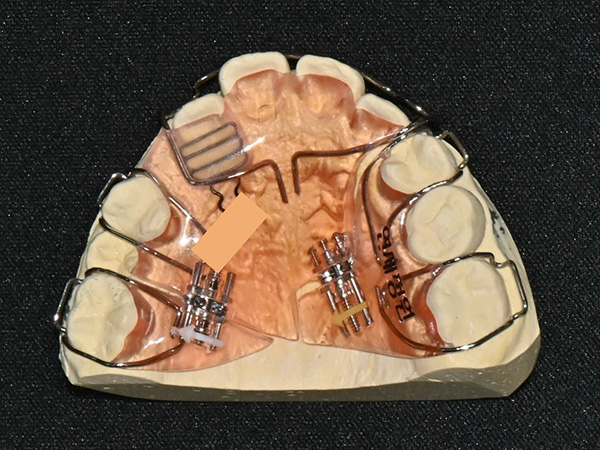

A patient had crowding in the upper canine area, a crossbite on one side, and a second premolar that was trapped and unable to erupt. Instead of waiting until adulthood (which might have required extraction-based orthodontics), we used a special removable appliance called a Sagittal Appliance to gently move the front teeth forward and molars backward, creating room for proper eruption.

This appliance includes push springs to move the incisors forward and distal screws to expand the space for the premolars—one of the most complex and precise devices to make!